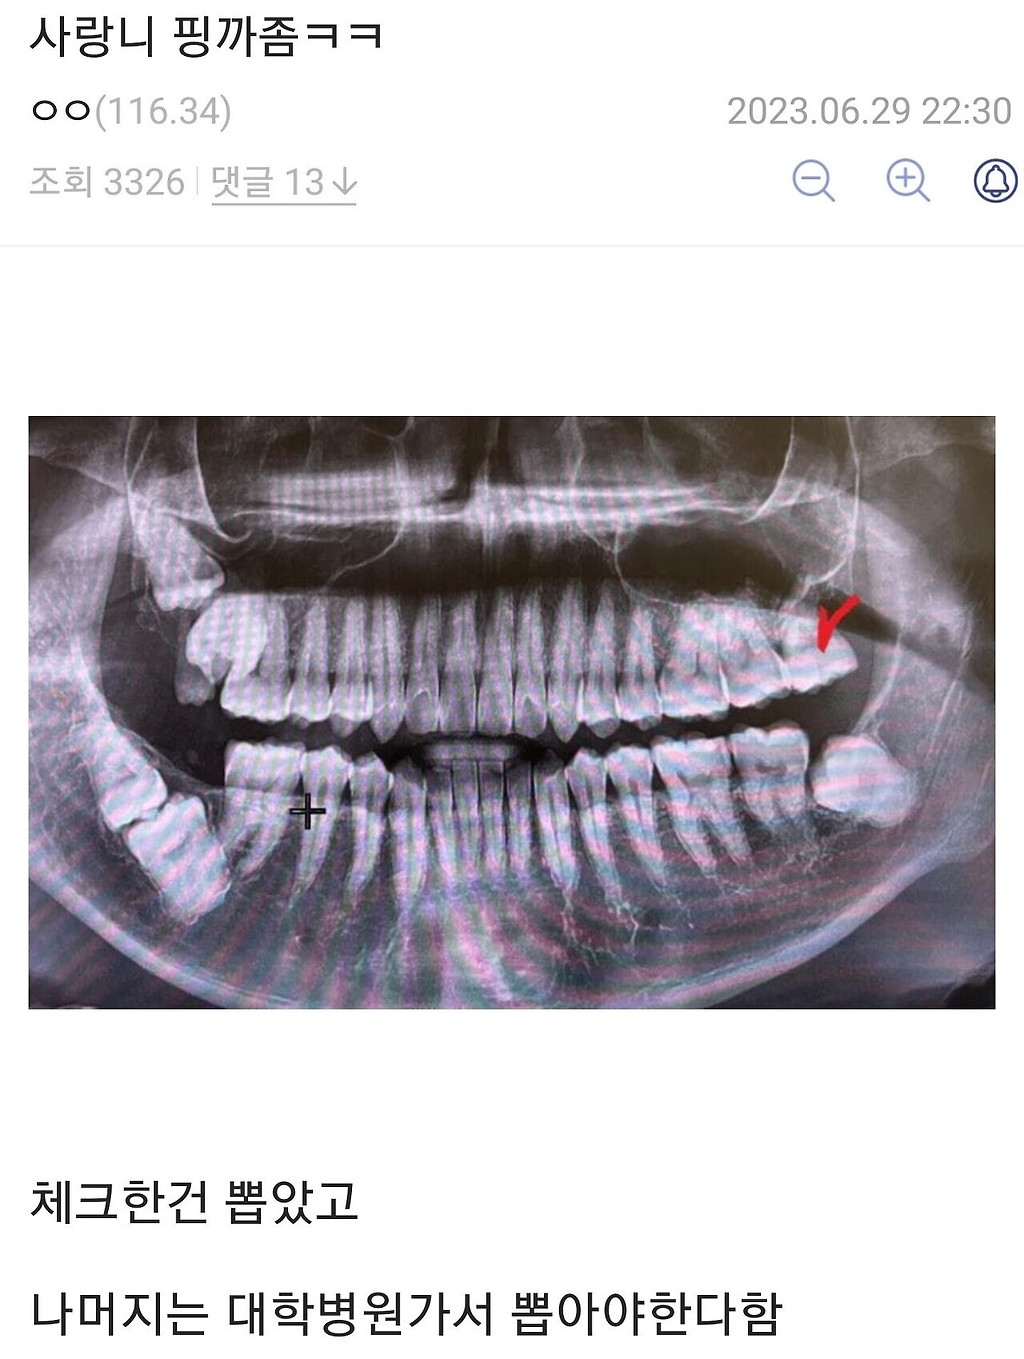

사랑니갤러리 레전드 모음